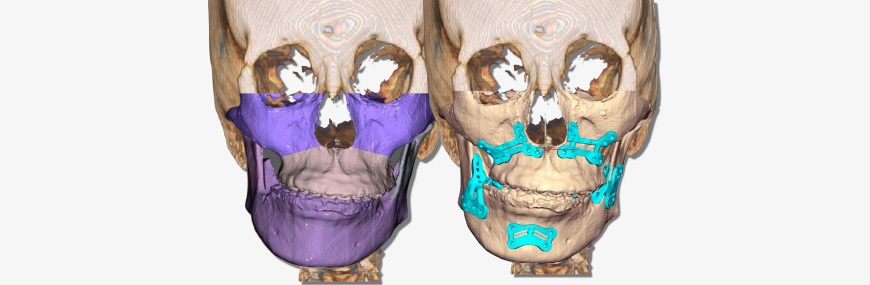

3D Jaw Setup & Review

- Send R2 STUDIO data & simple surgery plan to R2 Center & receive 3D jaw setup file within 24 hours

- Use FACEGIDE review program to confirm 3D jaw setup file

Saw Guides

- Customized for each patient to ensure precise bone incisions & deletions

FACEGIDE Plates

- Customized for each patient

- Reduced surgery time as no need to bend or cut customized plates